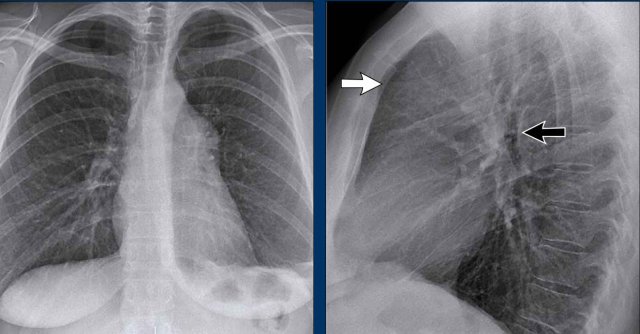

Spine Sign

When evaluating the vertebral bodies on the lateral view, they should appear progressively more radiolucent (darker) from top to bottom due to the increasing amount of aerated lung overlying them (white arrow).

If the lower thoracic vertebrae appear abnormally dense, it may indicate pathology in the lower lobes, such as consolidation or mass lesions — this is known as the spine sign.

Diaphragm Evaluation

• The right hemidiaphragm should be clearly visible anteriorly up to the chest wall (red arrow), representing the interface between aerated lung and abdominal soft tissues.

• The left hemidiaphragm is usually visible only up to the point where it is adjacent to the cardiac silhouette (blue arrow), beyond which the interface is lost due to the similar radiodensity of the heart and upper abdominal contents.